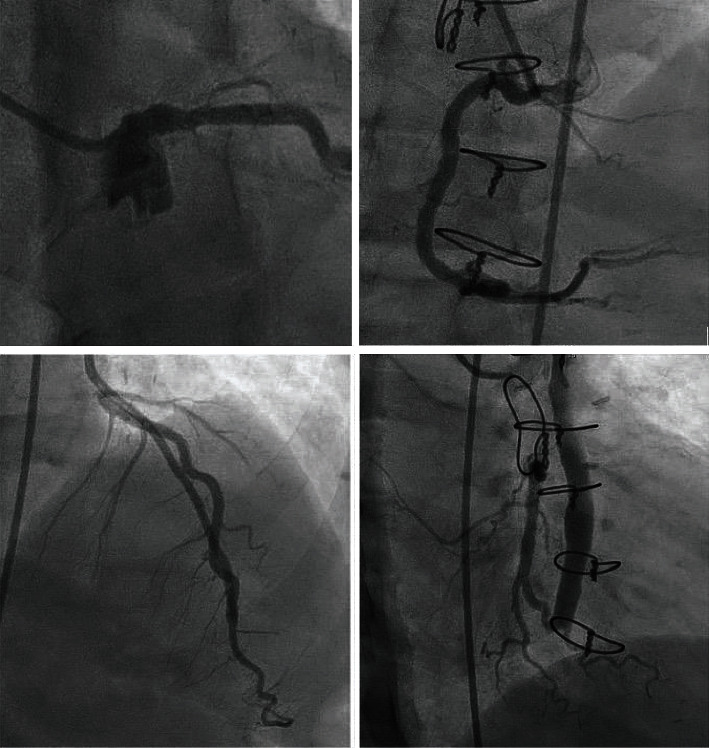

本病例是一名 59 岁的非裔美国女性,患有终末期肾病(ESRD),因胸部不适到急诊科就诊。她六个月前做过冠状动脉造影,结果显示心外膜冠状动脉没有闭塞性疾病。她的肌钙蛋白 I 水平升高,超声心动图显示新的区域室壁运动异常。她的 SARS-CoV-2 呈阳性。经过多学科团队会诊后,她接受了另一次冠状动脉造影检查,结果显示出现了新的严重多血管骨膜病变和左冠状动脉主动脉瘤。根据她的临床表现、血管造影结果和阴性的自身免疫检查结果,怀疑她患有与 COVID-19 相关的冠状动脉血管炎。该患者成功接受了冠状动脉旁路移植手术,术后恢复良好,未出现并发症。

We present the case of a 59-year-old African American female with end-stage renal disease (ESRD) who presented to the emergency department with chest discomfort. She had a coronary angiogram six months ago that showed no occlusive epicardial coronary artery disease. She had elevated troponin I levels and new regional wall motion abnormalities on echocardiogram. Her SARS-CoV-2 returned positive. After a multidisciplinary team approach, she underwent another coronary angiogram that showed new severe multivessel ostial lesions and a left main coronary artery aneurysm. COVID-19-related coronary artery vasculitis was suspected based on her clinical presentation, angiogram findings, and negative autoimmune workup. The patient underwent successful coronary artery bypass grafting and recovered without complications.